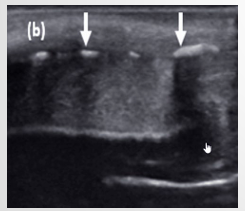

Longitudinal and Transverse images: Asterisk () demonstrates hypoechoic tumor which is confined to the subepithelial connective tissue and does not penetrate through or invade the tunica albuginea of the corpus cavernosa (arrows)*

Longitudinal view demonstrating hypoechoic SCC () invading through the echogenic line of the tunica albuginea (arrowheads)*